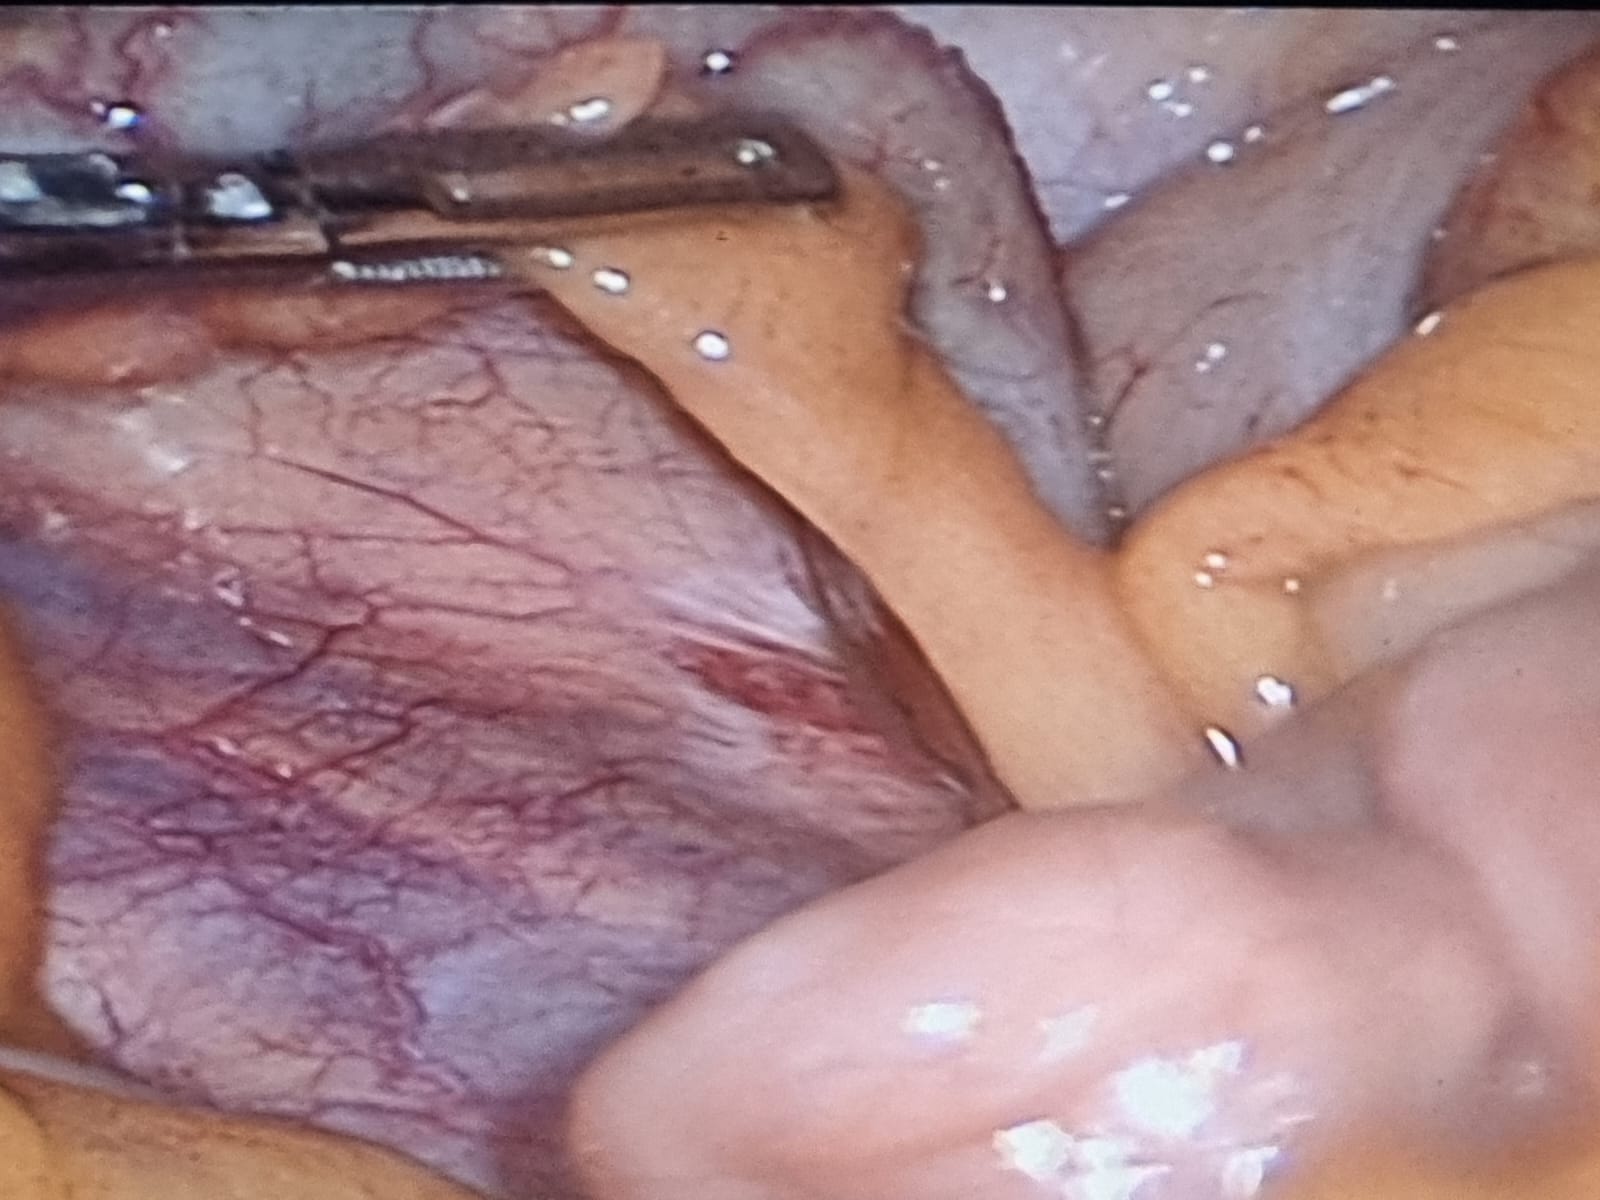

Patologías Quirúrgicas